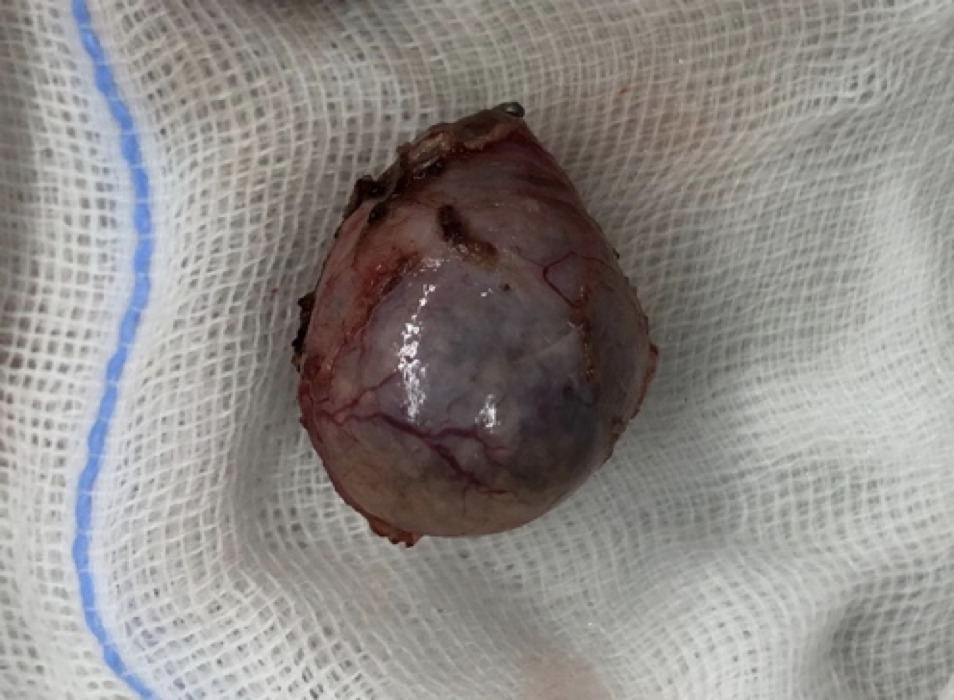

脾臓腫瘍

腫瘍が大きくなることでお腹の腫れなどを認めることがあります。また腫瘍が破裂することにより、腫瘍からの出血量によっては急性の虚脱や劇的な症状を伴うこともあります。

犬では血管肉腫が最も多い腫瘍であり、ジャーマンシェパードやレトリーバー種で発生が多いと言われています。

猫では脾臓の腫瘍は犬ほど多くはないが、猫では脾臓疾患の15%を肥満細胞腫という腫瘍が占めます。